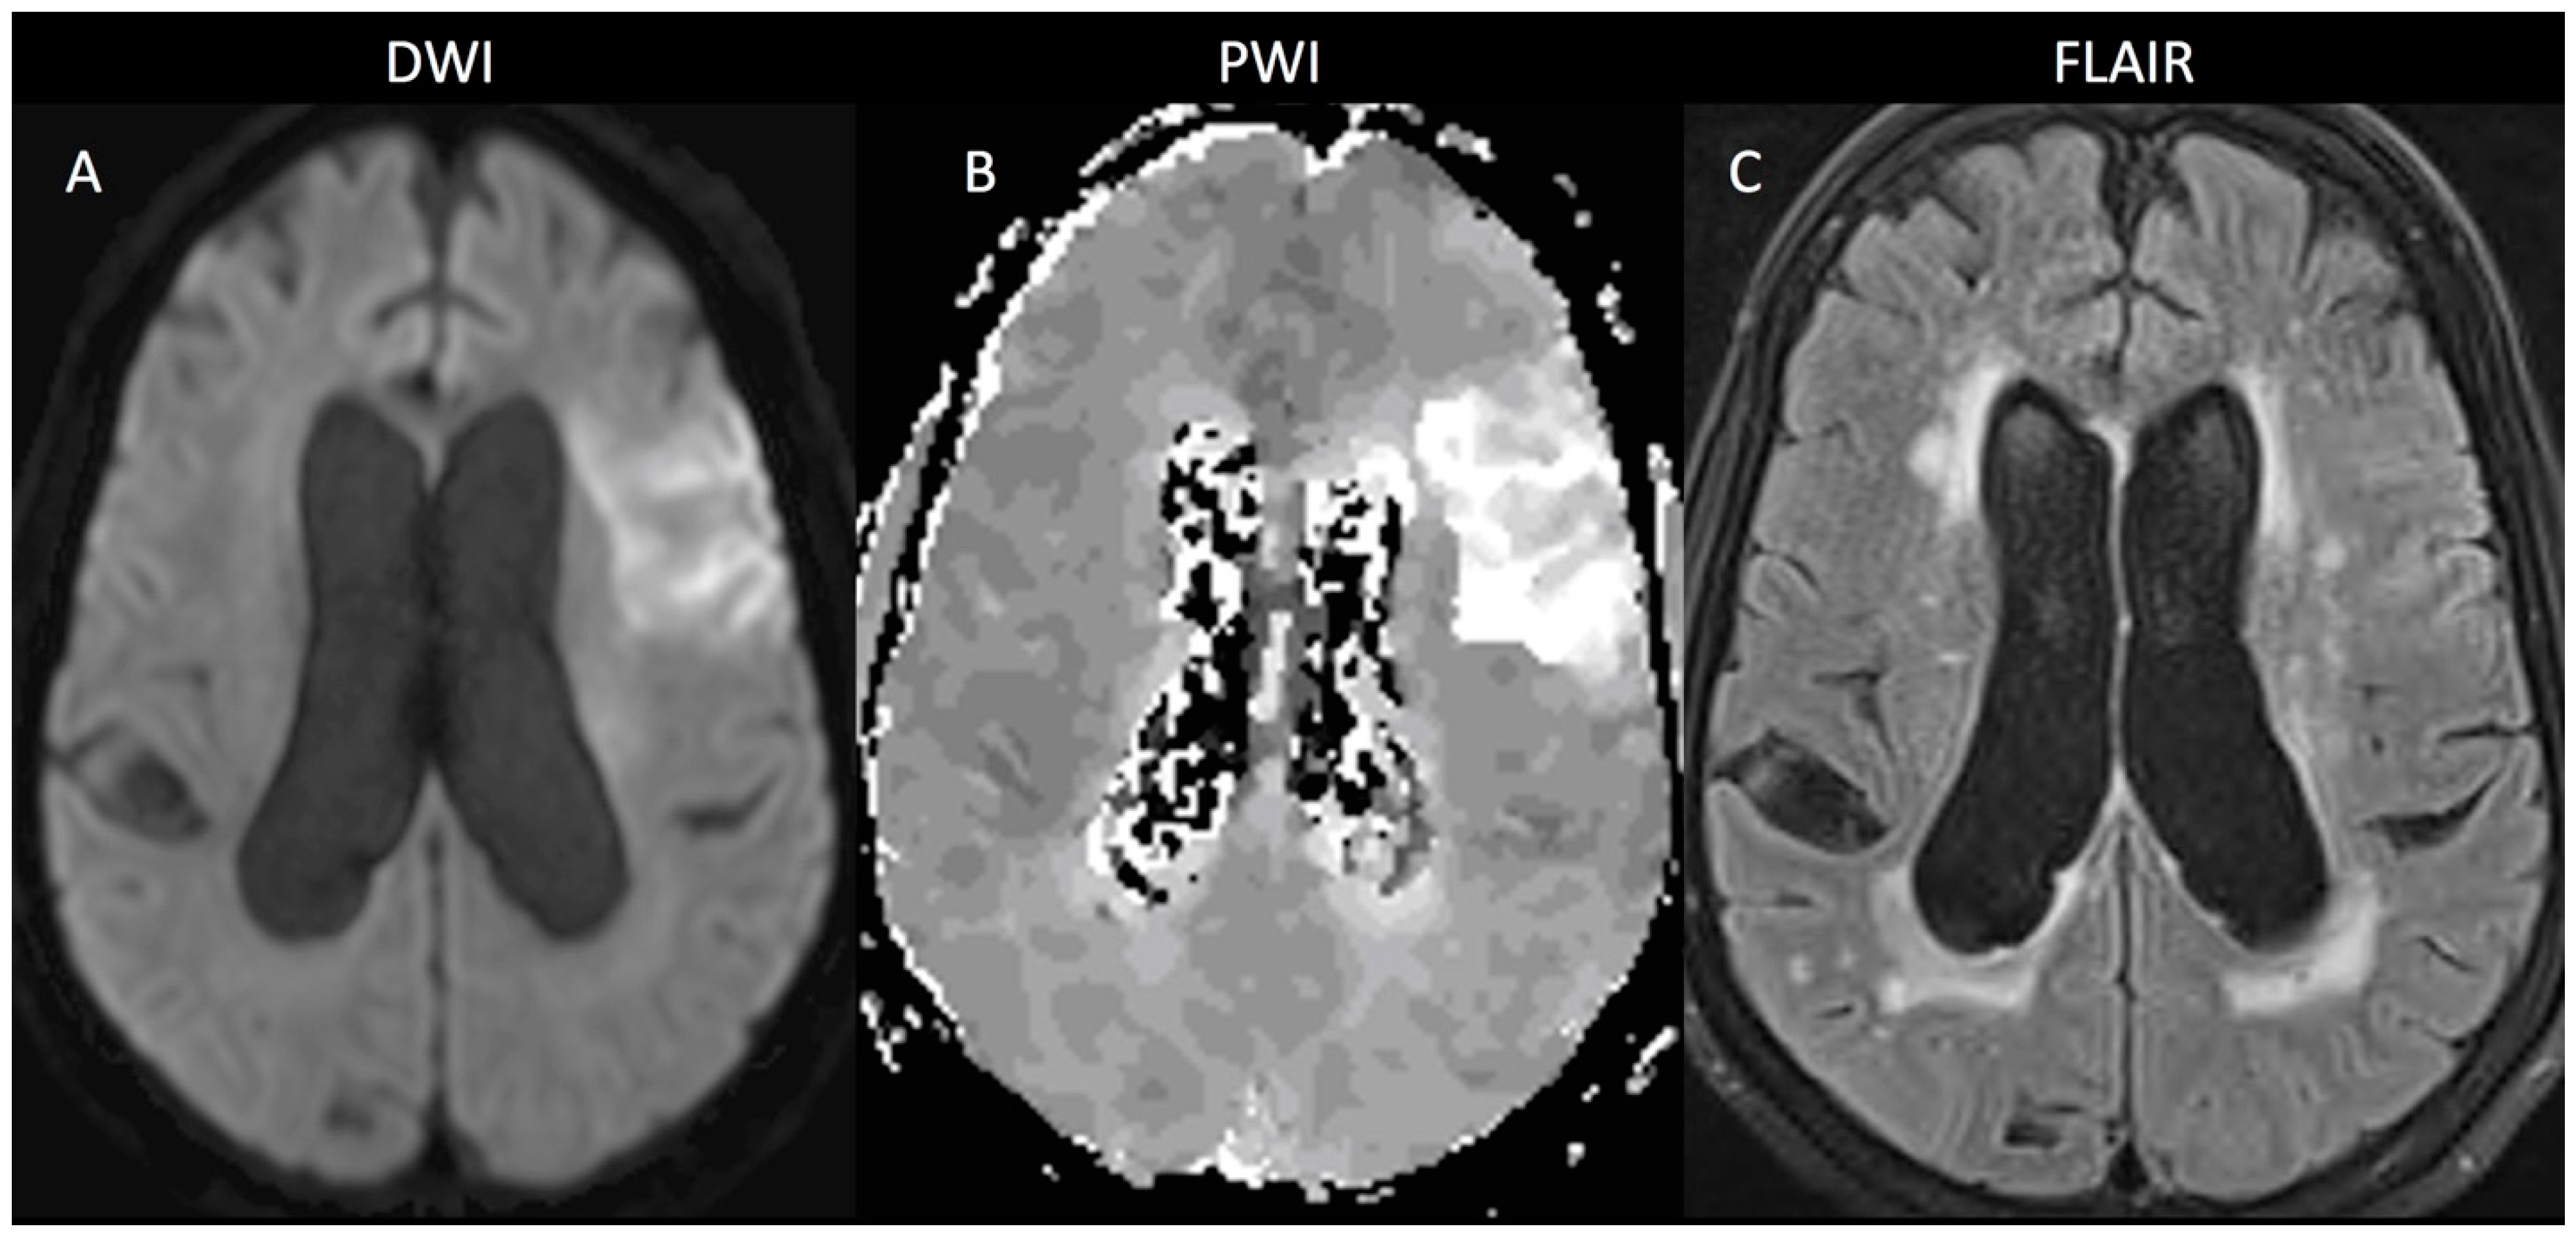

3.1.1. Imaging Findings